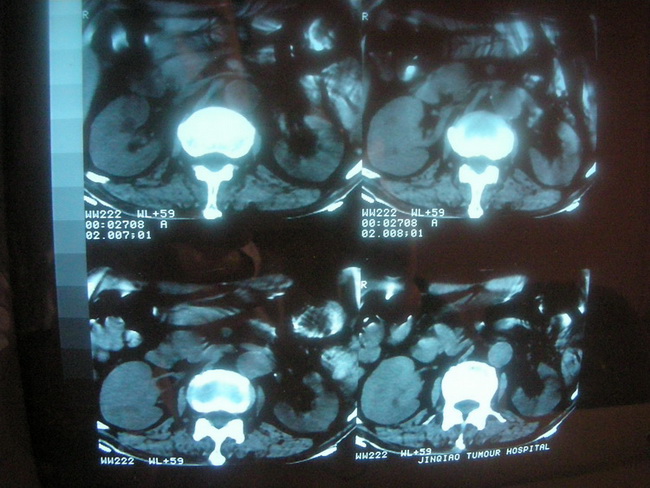

以下是引用卜一在2008-2-16 6:10:00的发言:[br]右肾增大,实质内明显见占位性病灶,并突出体外,密度不均匀。另双肺上叶见散在的斑片 索条及点状结节样致密影,右下肺门区不规则团块,右侧胸腔积液并形成局限性气胸。考虑:1 右肾癌。2 右肺门淋巴结转移及肺内 胸膜转移。3 右上肺陈旧结核。

以下是引用zjzjr在2008-2-16 14:15:00的发言:[br]1 右肾癌伴 右肺门淋巴结转移及肺内 胸膜转移。2右侧胸腔积液引流后改变(可见引流管影)3 双上肺继发型结核。